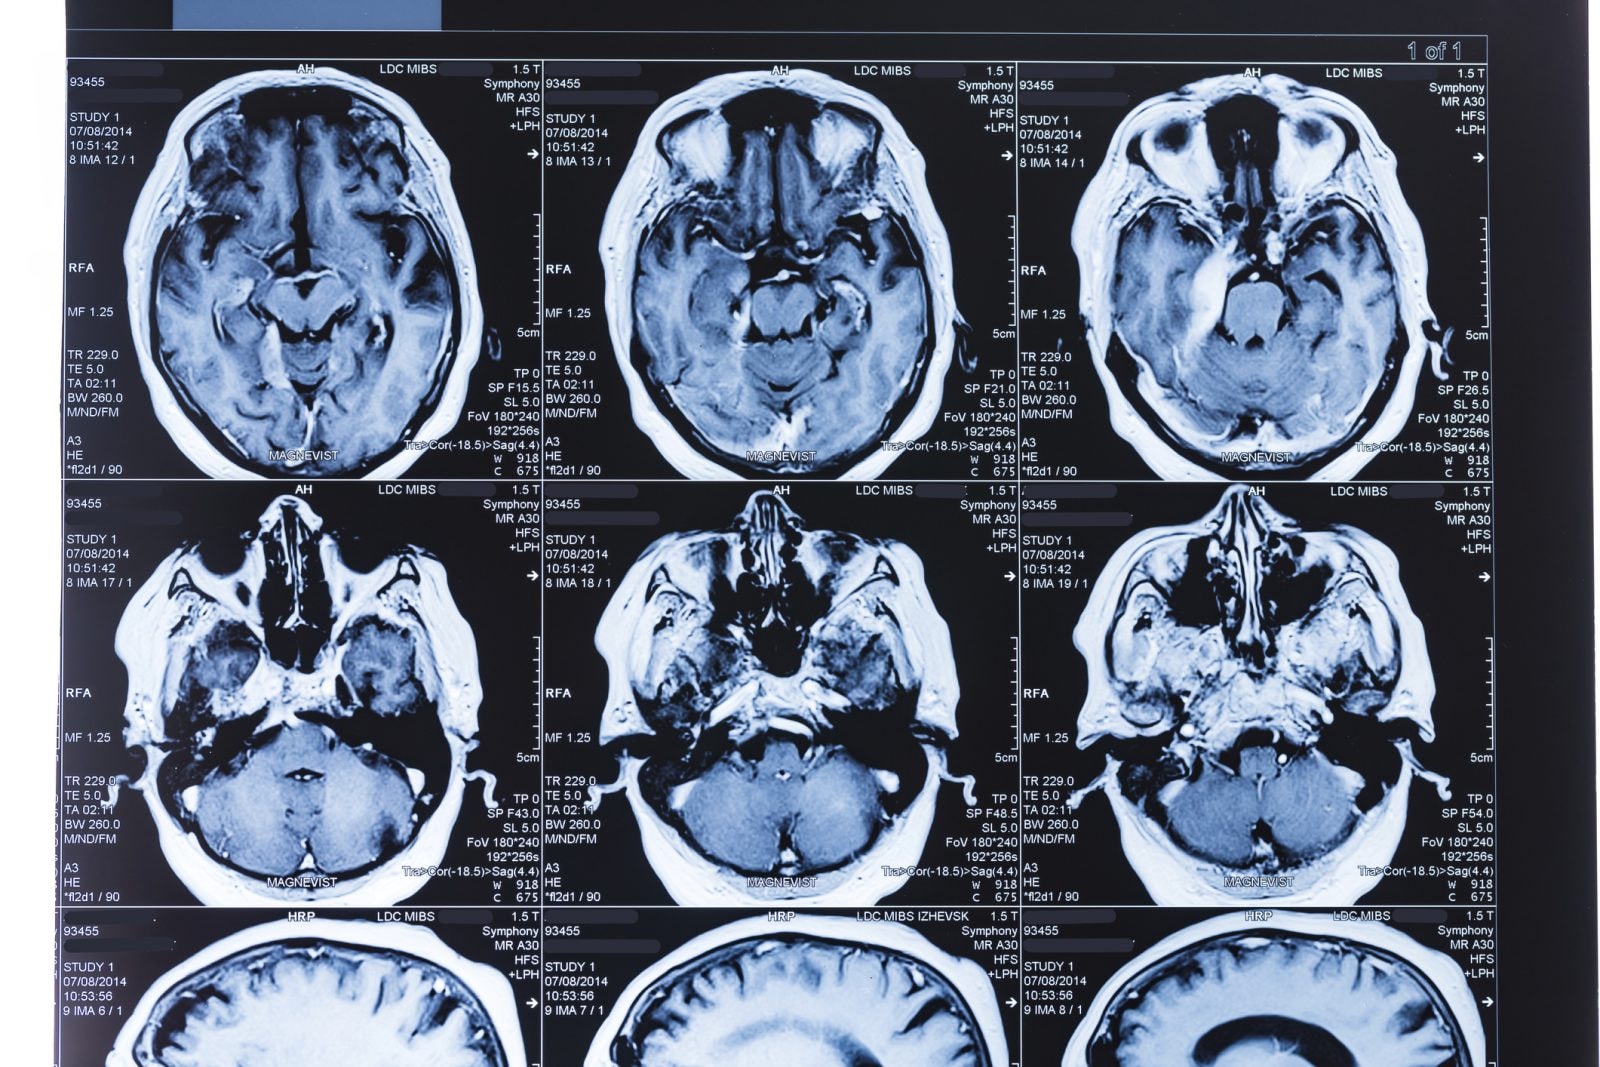

Zjawisko to wynika z nieprawidłowej reakcji układu odpornościowego, który zamiast wroga atakuje zdrowe komórki nerwowe. Prowadzi to do osłabienia mięśni a nawet paraliżu. Niektórzy pacjenci z COVID-19 cierpią na zapalenie mózgu. Nawet u tych młodszych, łagodnie przechodzących chorobę, zdarzają się wyniszczające ciało wylewy.

Badania na dużych grupach pacjentów z Francji i Chin potwierdzają obecność różnych symptomów neurologicznych nawet u 36 proc. zarażonych. W wielu przypadkach chodzi o umiarkowane i dość ogólne problemy w rodzaju bólu czy zawrotów głowy, wywołanych najczęściej przez silną reakcję obronną organizmu.

Są jednak sytuacje, gdzie symptomy sugerują, że wirus atakuje centralny układ nerwowy. Chodzi o utratę powonienia i smaku, osłabienie mięśni, drgawki i halucynacje. Lekarze zaobserwowali takie objawy u 46 do 84 proc. najcięższych przypadków.

Nieraz zmiany w świadomości pacjenta, jak dezorientacja, niezdolność skupienia uwagi i zaburzenia motoryczne czasem utrzymują się nawet u ozdrowieńców. Wszystko wskazuje, że SARS-CoV-2 infekuje mózg bezpośrednio albo wywołuje nieprawidłową reakcję układu odpornościowego, i to ona właśnie jest u podstaw zaburzeń neurologicznych.